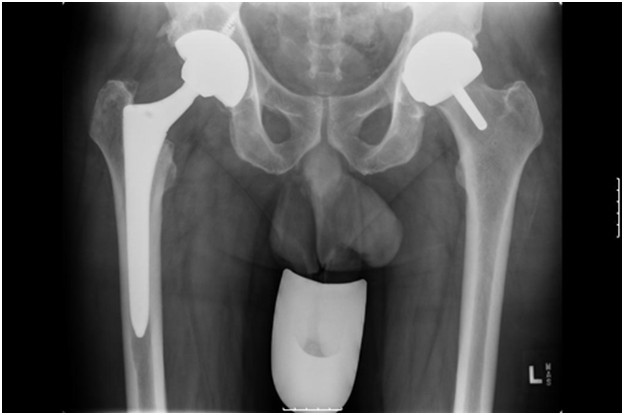

Poniżej przedstawiono radiogram stawów biodrowych u 45-letniego mężczyzny po alloplastyce obustronnej stawów biodrowych. Który z opisów tego radiogramu jest prawdziwy?

Pytanie 69